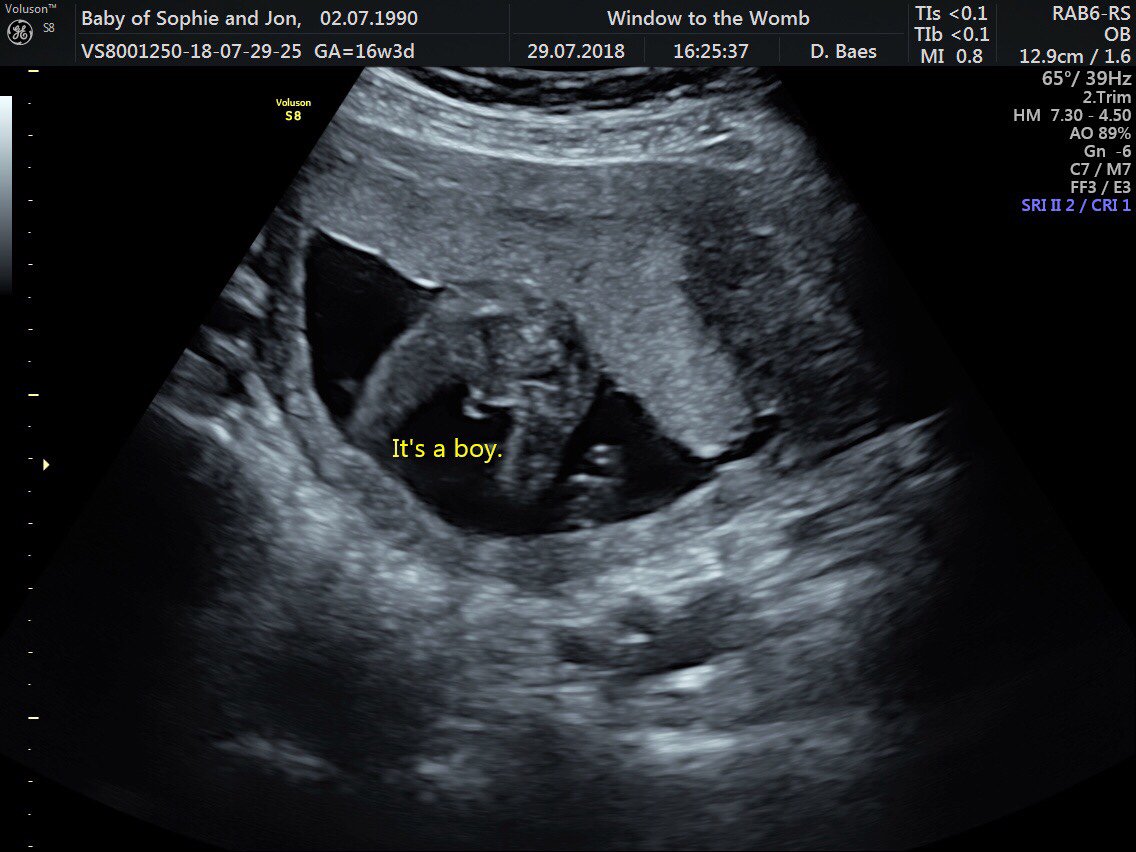

Baby Boy Potty Shot 13 Weeks . The bladder is more likely to be seen in a boys potty shot due to their low bladder position and their genitals being on top of their lower abdomen. I had a shot like that at 13 weeks, and our tech told us there was no gender in that shot. I’d honestly wait until you can get one at. I could see their penis clear as. I know it’s still really early and we may not even been able to tell. Your baby’s sex will not change but their genitalia is still developing and will certainly undergo changes in the next few weeks. Get the blood test or wait until your anatomy scan. People of the internet are no better at guessing your child’s sex than ultrasound. We just had it confirmed boy. She said she wasn't certain if it was a cord or penis. Unfortunately these aren't the potty shots you need at 13weeks. 13 week potty shot (from a few weeks ago). I was 13 weeks exact and she gave us a potty shot is this a boy or girl? Fwiw, i don’t have print outs but i did see potty shots of my boys at 12w and each time it was incredibly obvious that they were boys. Jul 8, 2020 at 2:11 pm.

The bladder images as a black circle under the penis and scrotum and to an untrained eye may look like the anus. I had a shot like that at 13 weeks, and our tech told us there was no gender in that shot. Unfortunately these aren't the potty shots you need at 13weeks. People of the internet are no better at guessing your child’s sex than ultrasound. I was 13 weeks exact and she gave us a potty shot is this a boy or girl? I know it’s still really early and we may not even been able to tell. 13 week potty shot (from a few weeks ago). Fwiw, i don’t have print outs but i did see potty shots of my boys at 12w and each time it was incredibly obvious that they were boys. Your baby’s sex will not change but their genitalia is still developing and will certainly undergo changes in the next few weeks. I’d honestly wait until you can get one at.

Baby Boy Potty Shot 13 Weeks We showed the pic to the nurse at our on office, and she said totally a boy. The bladder images as a black circle under the penis and scrotum and to an untrained eye may look like the anus. We showed the pic to the nurse at our on office, and she said totally a boy. I know it’s still really early and we may not even been able to tell. She did the blood doppler thingy and it was red/. She said she wasn't certain if it was a cord or penis. 13 week potty shot (from a few weeks ago). I could see their penis clear as. Get the blood test or wait until your anatomy scan. Fwiw, i don’t have print outs but i did see potty shots of my boys at 12w and each time it was incredibly obvious that they were boys. Penises and clitorises are close to the same size until around 14 weeks. Jul 8, 2020 at 2:11 pm. The bladder is more likely to be seen in a boys potty shot due to their low bladder position and their genitals being on top of their lower abdomen. People of the internet are no better at guessing your child’s sex than ultrasound. I’d honestly wait until you can get one at. Unfortunately these aren't the potty shots you need at 13weeks.